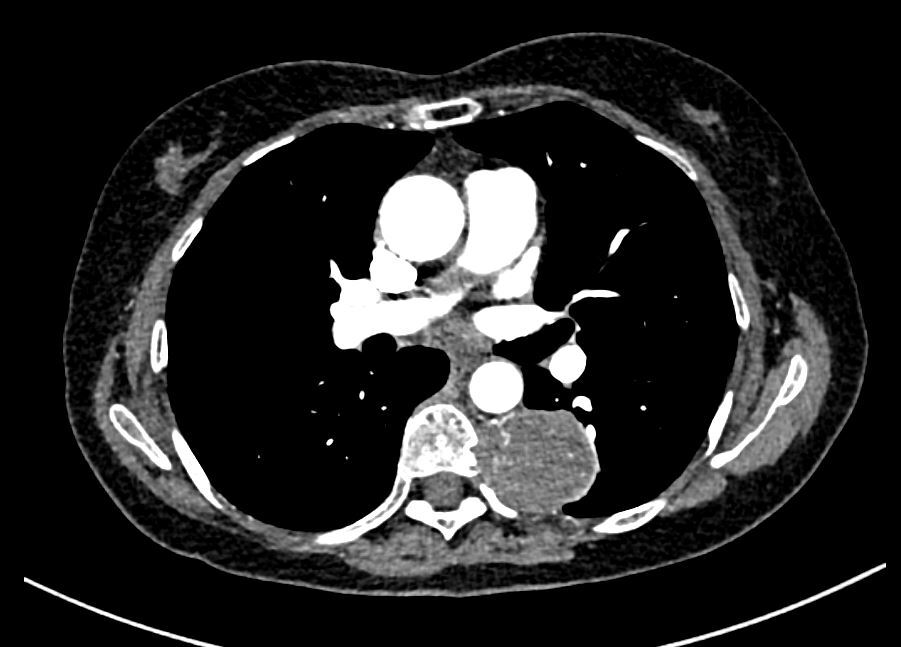

體檢發(fā)現(xiàn)前縱膈腫物,比較重要的檢查有胸部增強(qiáng)CT和磁共振檢查。胸部增強(qiáng)CT:了解瘤體和周圍器官(如:重要血管)的關(guān)系,醫(yī)生便于評估手術(shù)難度、制定“作戰(zhàn)計(jì)劃”;磁共振:可以分辨是實(shí)性腫瘤?還是囊性腫物(“一包水”)?1實(shí)性腫瘤往往建議積極手術(shù),較大者往往侵犯周圍重要組織器官,手術(shù)復(fù)雜程度還有疾病嚴(yán)重程度都可術(shù)前預(yù)判2囊腫則預(yù)判手術(shù)不那么緊迫,可以視瘤體大小決定手術(shù)時(shí)機(jī),往往侵犯力、手術(shù)復(fù)雜度比實(shí)性腫瘤好。